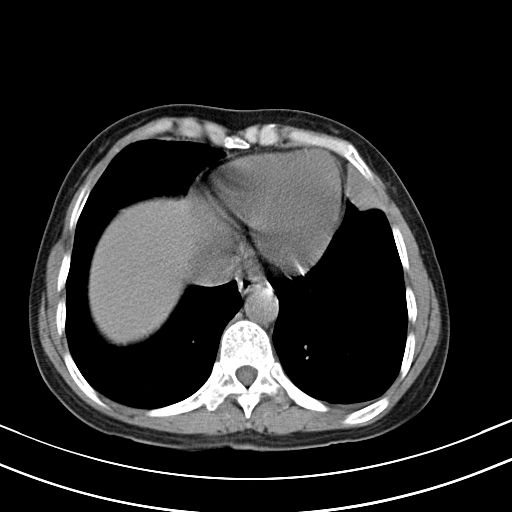

女,47岁,咳嗽胸痛一个星期,我们考虑肺结核,左下肺病灶肿瘤像不像,请高手指点。急。

右肺考虑炎症,建议抗炎后复查,左肺下叶考虑肺不张。

考虑炎性病变,左肺舌叶病灶需要与早期肺脓肿鉴别(结合实验室),左侧少量胸腔积液。

左上肺舌叶实质性病变,形态呈楔形,内可见支气管气像,中至重度强化,考虑为炎性改变,建议复查

1)右肺上叶前段及左肺上叶舌段感染性病变;建议抗炎治疗后复查。2)左侧少量胸腔积液。

考虑右肺上叶前段及左肺舌叶炎症,建议抗炎治疗后复查除外结核。

左肺舌叶病灶呈扇形分布,其内可见支气管影,胸膜面光滑,不支持肿瘤病变。